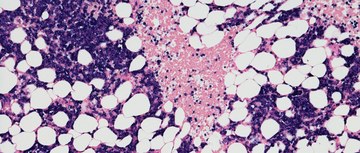

Myelofibrosis with anemia

Drug Updates

Pharmacist's Application to Practice: Momelotinib

Diana Mansour, PharmD, BCOP, Clinical Pharmacy Specialist, Charles M Gallagher, PharmD, PGY2 Oncology Pharmacy Resident; Kelsea Seago, PharmD, BCOP, Clinical Pharmacy Specialist, allfrom WVUH Hospitals, write about Momelotinib.